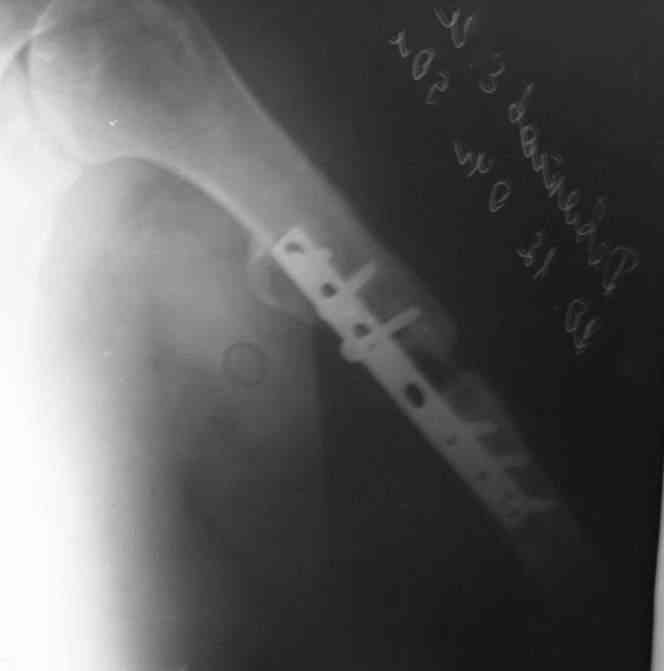

Штифт - отвисание проксимального отдела - накостный остеосинтез, нагноение, АФВ с ревизиями раны, опять пластина и снова нестабильность. Была удалена пластина и выполнен БИОС штифтом ChM (ДЕОСТ). Через 2 нед. пациент сел за руль и вышел на работу. Причем так и работает до сих пор уже 1,5 года, хотя полного сращения мы вроде бы не достигли ( снимки пришлю позже) - пациент не приходил на осмотры, общался только по телефону.

Второй пациент перенес два неудачных накостных остеосинтеза на фоне пареза лучевого нерва. Была удалена пластина и выполнен БИОС штифтом ChM (ДЕОСТ) - это была наша первая операция БИОС.